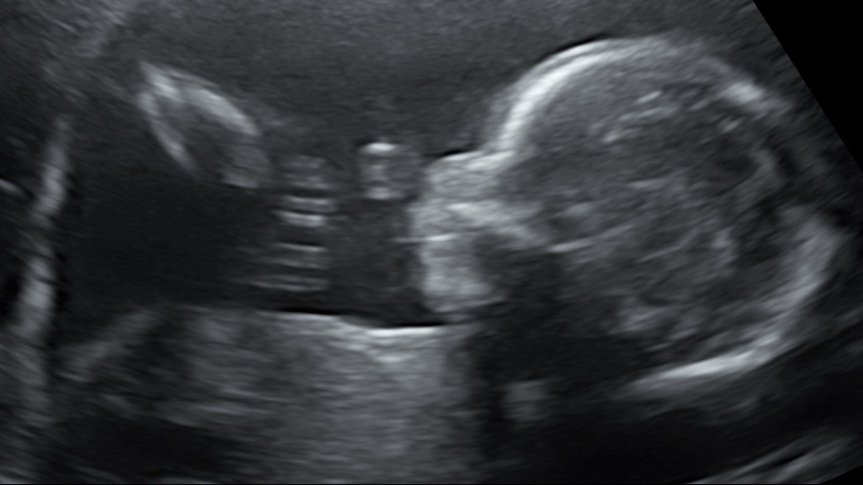

21 weken